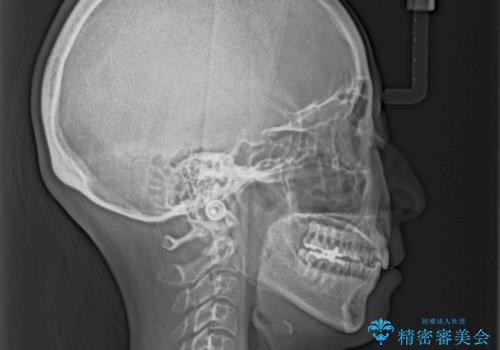

- 下顎の八重歯と、上下のクロスバイトを気にして来院された患者様です。

インビザラインを用い、下顎全体の後方移動、IPR(歯と歯の間を削る)と歯列全体を拡大させることで、歯並びを整えていくこととしました。

奥に位置していた上の前歯が下の前歯を乗り越える際、奥歯でものを咬むことができず、辛い時期が続きました。